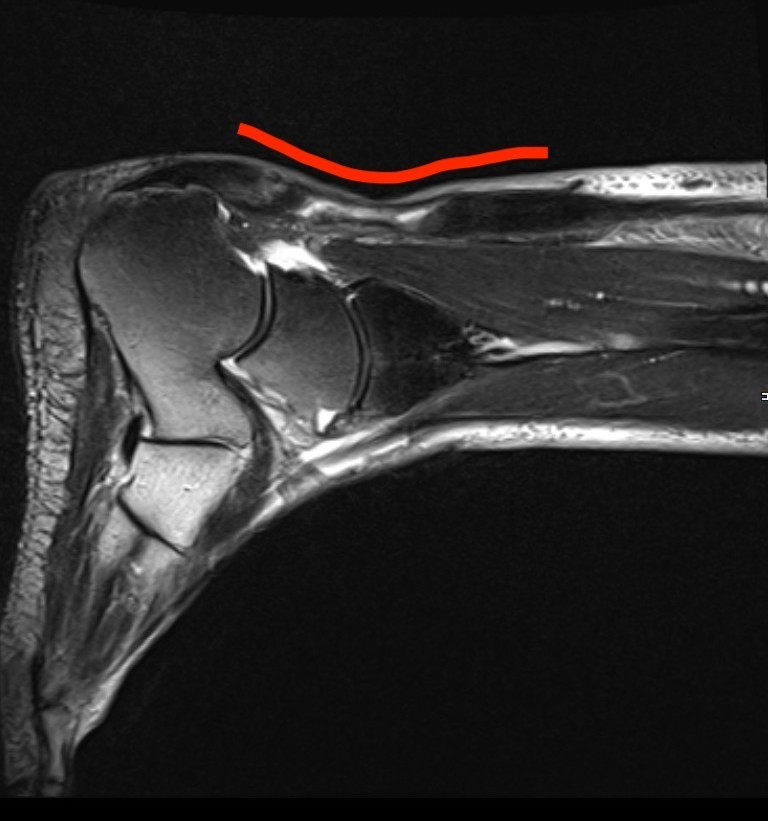

断裂から3ヶ月経過した陳旧性アキレス腱断裂

他院で保存療法を行うも腱は繋がっておらず、大きな陥凹を認めます(赤矢印)

MRI画像:アキレス腱は繋がっていないと整形外科で診断していただきました。

患部を観察すると、アキレス腱部には大きな陥凹があり、腱は繋がっていませんでした。

信頼できる整形外科でMRI検査を行なっていただきましたが、「腱はつながっておらず今後改善するものではない」と回答をいただきました。